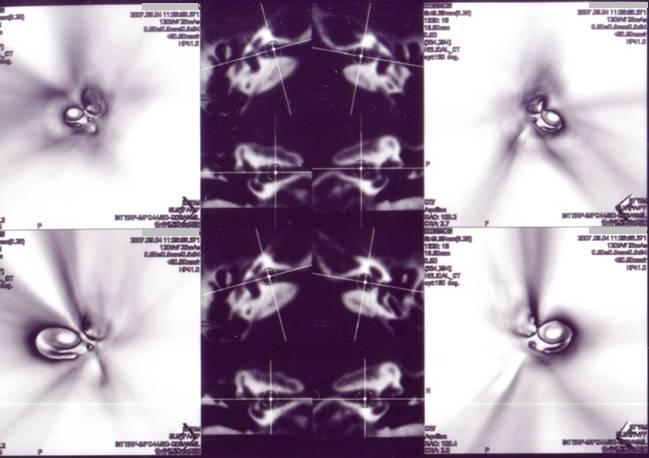

神経鞘腫は内耳道内に発生することが多いのでチェックしたが、内耳道内には異常は認められなかった(図16)。

V.Eの観察方向(図17)

図16

図17